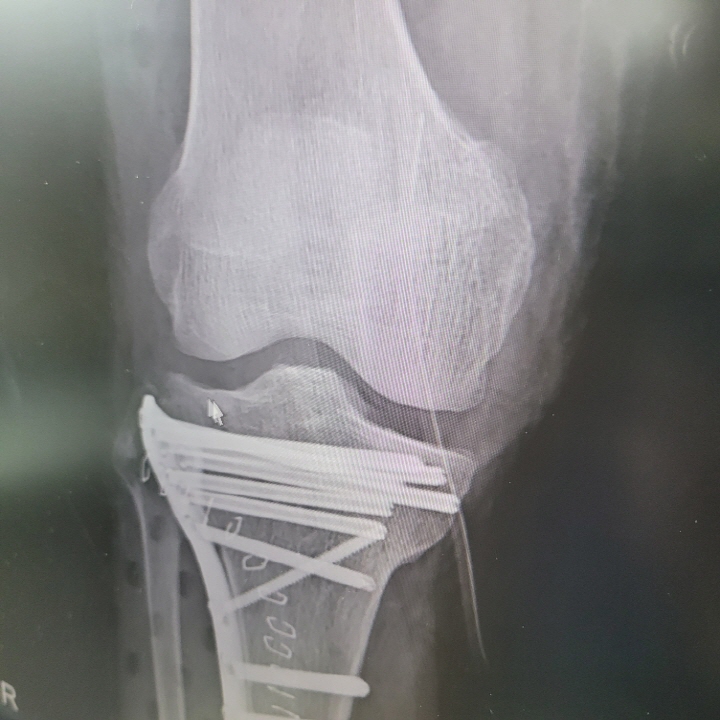

1년 전 사고로 인해 무릎 경골 상단 골절로 인해 금속판과 핀 고정술을 받은 지인의 경우, 이번에 1년이 경과하여 담당 의사의 판단으로 최근에 핀 제거 수술을 받았습니다.